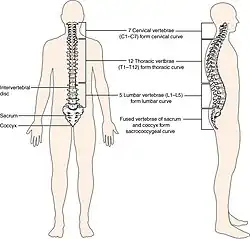

The spinal cord is housed in a bony hollow tube called the vertebral column.[3] The vertebral column is composed of many ring-like bones called vertebra (plural: vertebrae) and it spans from the skull to the sacrum. Each vertebra has a hole in the center called the vertebral foramen through which the spinal cord traverses.[3]

Laminae (singular: lamina) are the anatomical structures of primary importance in a laminotomy. Laminae are part of the vertebral arch which is the region of bone on the back side of each vertebra that forms a protective covering for the back side of the spinal cord.[3]

The vertebral arch is composed of several anatomical features in addition to laminae that must be taken into account when performing a laminotomy. In the center of the vertebral arch is a bony projection called the spinous process.[3] The spinous process is located on the posterior or back side of the vertebra and serves as the attachment point for ligaments and muscles which support and stabilize the vertebral column.[3] Each vertebra has two lateral bony projections called the transverse processes which are located on either side of the vertebral arch. Transverse processes come into contact with the ribs and serve as attachment points for muscles and ligaments that stabilize the vertebral column.[3] The lamina is the segment of bone that connects the spinous process to the transverse process. Each vertebra has two lamina, one on each side of the spinous process.[3]

- Cervical laminotomy is performed on cervical vertebrae, the ones closest to the head.[3]

- Thoracic laminotomy is performed on thoracic (middle) vertebrae.[3]

- Lumbar laminotomy is performed on lumbar vertebrae, the ones closest to the sacrum.[3]